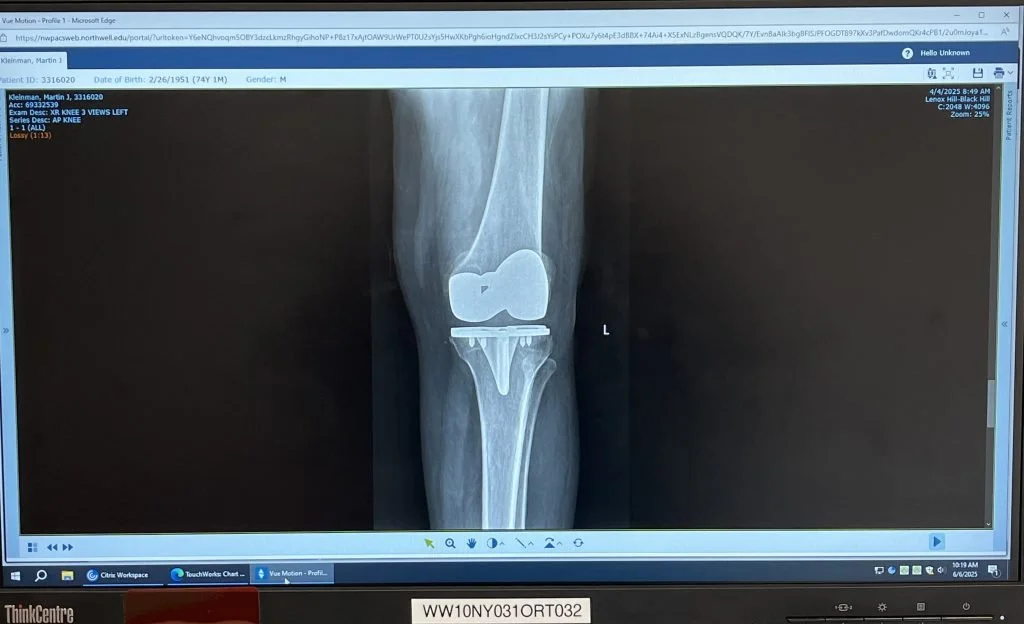

That’s my new knee. See the titanium plates, and screws? Pretty cool, huh?

My surgeon explained the post-op deal: two weeks of at-home rehab (a guy came twice a week to get me walking and doing my exercises up and down the hall), and twice daily stretching and bending with a yoga strap, weights, heating pads, ice packs, etc. My wife was my at-home tech, and she killed me. “C’MON!” she’d push. “DO THIS!”